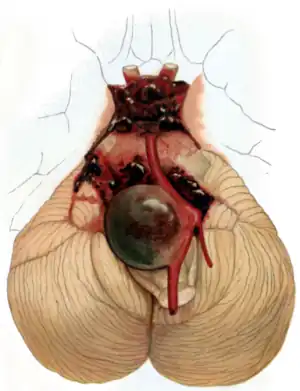

Aneurysm of the basilar artery and the vertebral arteries.